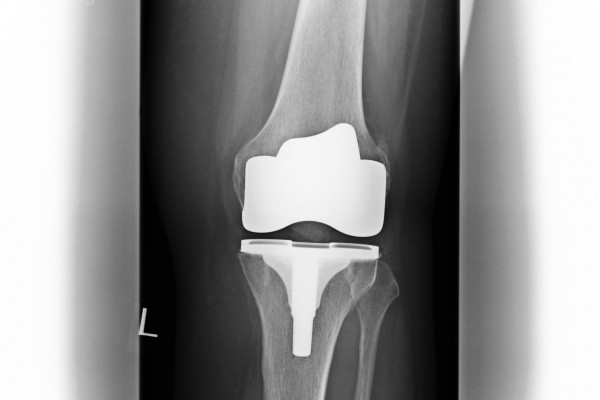

Oberflächenersatz („Knie-TEP“)

Bei einem Verschleiß der gesamten Knorpelfläche bei noch intakten Seitenbändern empfehlen wir einen Oberflächenersatz.

Hierbei werden nur wenigen Millimeter vom Knorpel entfernt um das Implantat passgenau aufzubringen.

Um eine noch höhere Präzision und die bestmögliche individuelle Anpassung des Implantates zu gewähren, bieten wir die Möglichkeit einer individuellen Schnittblockplanung vor der Operation an (Nähere Auskünfte erhalten Sie in der Spezialsprechstunde von Dr. med. Michael Matzer).